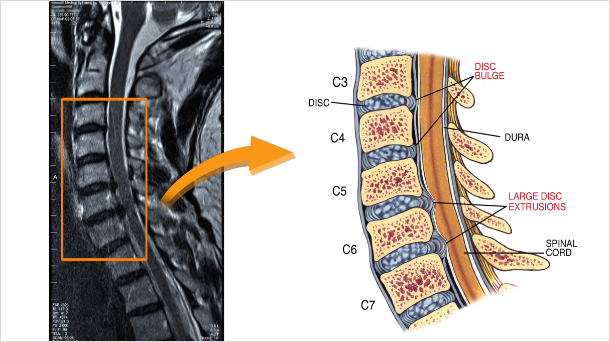

목디스크

경추 뼈와 뼈 사이의 추간판이 탈출하거나 파열돼 목을 지나가는 척추 신경을 눌러 통증이 느껴지는

질환입니다.

경추추간판탈출증인 목디스크는 목 뼈와 뼈 사이의 디스크가 제자리에서 이탈되어 신경을 압박하거나, 뼈 조직이

비정상적으로 자라 목을 지나가는 척추 신경이 눌려서 통증을 느끼는 질환입니다. 과거에는 주로 40~50대에서

주로 나타났지만, 컴퓨터를 시작하는 나이가 점점 어려지며 최근에는 20~30대에서도 목디스크 환자가 급격하게

늘었습니다.